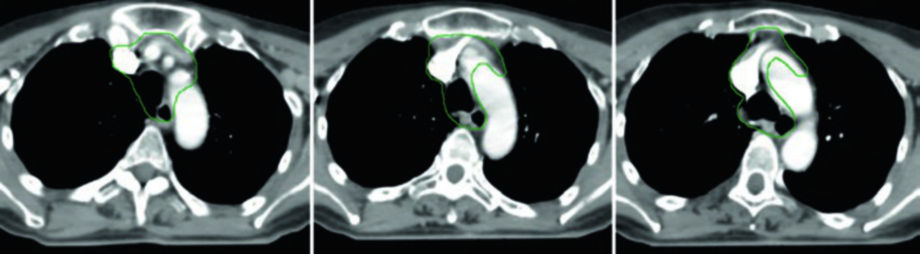

Caso 5 — Câncer pouco diferenciado, fenótipo folicular (Fig. 9.5): Mulher de 69 anos com câncer de tireoide pouco diferenciado de fenótipo folicular, aderido a traqueia e esôfago, submetida a ressecção e iodo radioativo, que recorreu com massa paratraqueal direita invadindo a traqueia. Após nova ressecção e esvaziamento cervical, recebeu quimiorradiação adjuvante. O CTV60 Gy (verde) cobre o compartimento central e o mediastino superior. O tratamento do pescoço lateral foi omitido, dada a alta probabilidade de recorrência no compartimento central — a dose e o risco foram priorizados onde o benefício clínico era máximo.